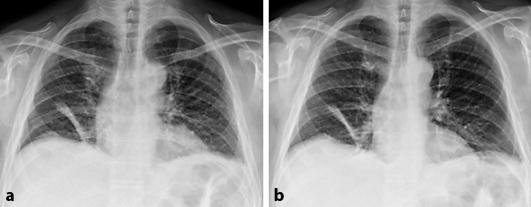

A 55-year-old male presented with orthopnea and aphonia after an episode of bilateral shoulder pain preceded by an upper respiratory tract infection. Spirometry, chest X-ray and videolaryngoscopy revealed bilateral and simultaneous paresis of the diaphragm and the vocal cords. Clinical examination at admission and at the 2-month follow-up did not show upper limb weakness or atrophy, except for a mild atrophy of the right supraspinatus muscle. An electromyography of the upper limb muscles and nerve conduction studies did not reveal signs of denervation. Analysis of the cerebrospinal fluid and an MRI of the neuraxis were unremarkable. After treatment with prednisolone, vocal cord function markedly improved within 8 weeks, whereas paresis of the diaphragm persisted.

一名55岁男性,在上呼吸道感染后出现双侧肩部疼痛,随后出现端坐呼吸和失音。肺活量测定、胸部X线检查和电子喉镜检查显示双侧膈肌和声带同时麻痹。入院时及2个月随访时的临床检查未发现上肢无力或萎缩,仅右侧冈上肌轻度萎缩。上肢肌肉的肌电图和神经传导研究未发现失神经迹象。脑脊液分析和神经轴MRI检查无异常。使用泼尼松龙治疗后,声带功能在8周内明显改善,而膈肌麻痹持续存在。